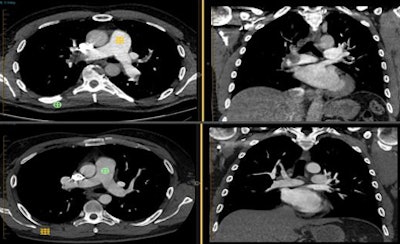

![]() |

| No differences in image quality are perceived between the two protocols. (Top row) 62-year-old man with acute onset of chest pain underwent a reduced-contrast spectral dual-energy protocol: 50 kV, signal-to-noise ratio = 17:1, contrast-to-noise ratio = 14:1, and 22 cc of iodinated contrast. (Bottom row) 58-year-old man with new-onset dyspnea received a conventional PE rule-out protocol: 100 kV, signal-to-noise ratio = 14:1, contrast-to-noise ratio = 12:1, and 50 cc of iodinated contrast. |